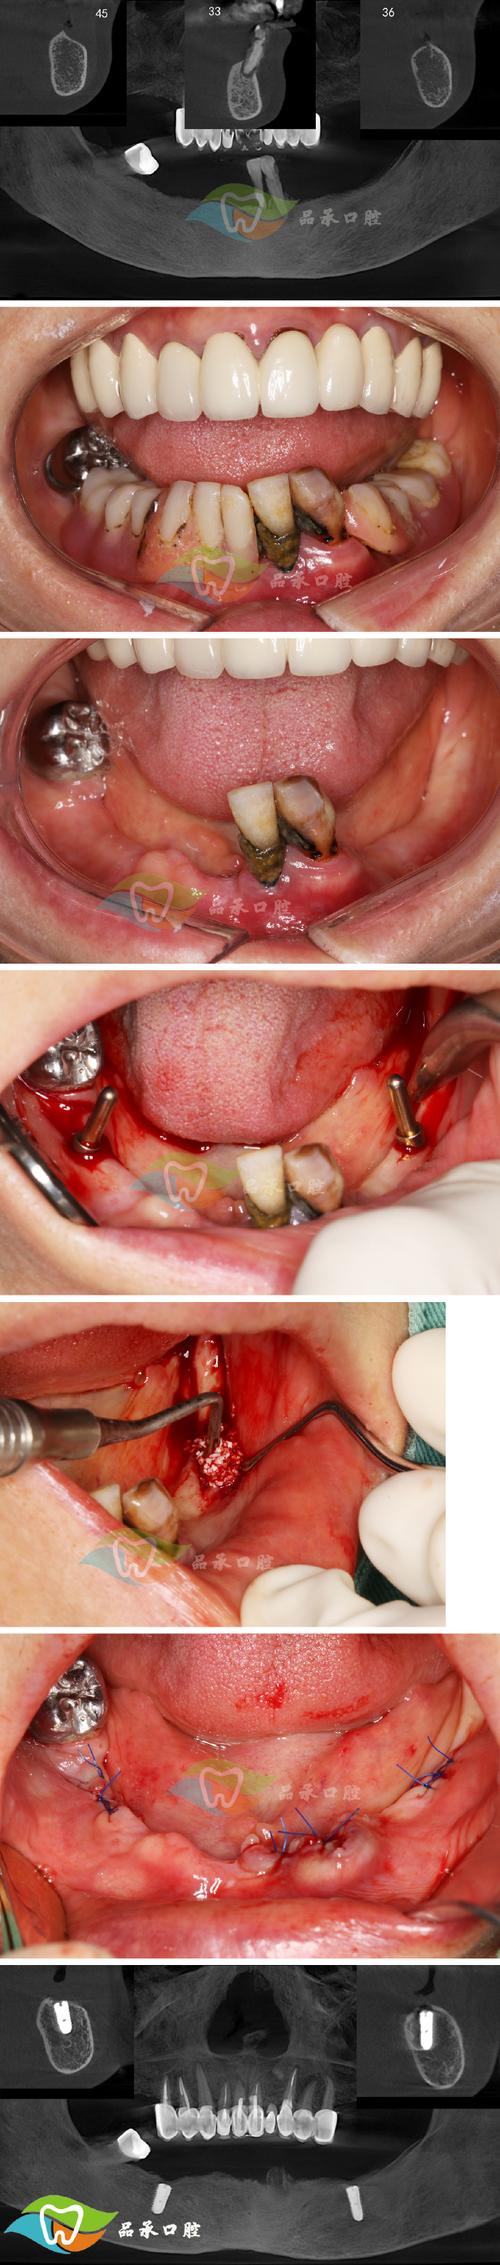

种植牙的流程通常包括术前检查、方案设计、种植手术、戴牙冠及术后维护五个阶段,术前需进行全面的口腔检查(含CBCT拍片、血常规等),评估牙槽骨密度、高度及全身健康状况,排除种植禁忌症;医生根据检查结果制定个性化方案,明确种植体型号、植入位置及修复方式;手术阶段在局部麻醉下进行,通过微创技术将种植体植入牙槽骨,过程约30分钟-1小时,创伤小、恢复快;术后3-6个月待种植体与牙槽骨骨结合完成后,安装基台并制作牙冠(全瓷冠、烤瓷冠等),最终完成修复,整个过程中,数字化技术的应用可缩短治疗周期,部分患者可实现“当天种牙、当天戴冠”的即刻负重效果。